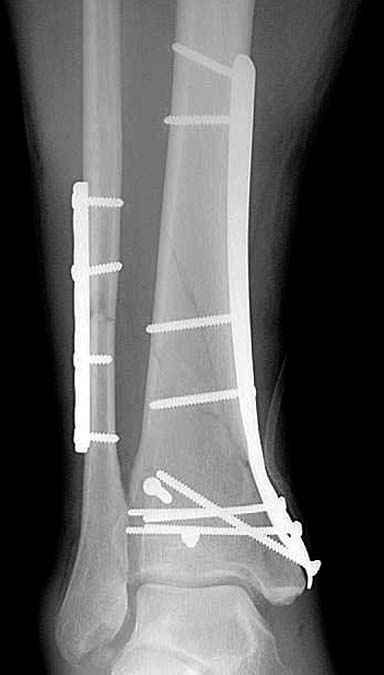

Данная фиксация пластинами сделана классическим АО методом описанным еще в 1989 году в книге J. Mast и R. Ganz “Planning and Reduction Technique in Fracture Surgery”. В то время antiglade method DCP пластиной в 4.5 мм c повторением натурального изгиба голени в н/3 считался одним из оригинальных. Повторение оригинальной концепции и фиксация спонгиозными шурупами в дистальном отделе доказывает, что коллеги хорошо освоили метод АО. Но для уменьшения раздражения пластиной изнутри в нижнем отделе, авторы применяли технику погружения пластины в кортекс. Профилактические меры не всегда помогали, и в неумелых руках "передне-медиальный АО доступ" часто осложнялся кожными осложнениями.

Приход анатомических преконтурированных тонких пластин с угловой стабильностью изменил методику лечения низких переломов. Современные пластины устанавливаются из минидоступов и разделяются на правые и левые. Можно установить латерально, медиально или спереди в полиаксиальных направлениях.

Без современных материалов создать хорошую фиксацию становится трудной задачей, и этот случай характерен тем, что достигнутую идеальную репозицию испортили старомодной техникой. Исследования показали, что спонгиозные шурупы в метафизарных частях не создают механические преимущества как считали раньше. Кортикальные винты менее агрессивны и не оставляют дефекта кости после их удаления.

Низкопрофильные преконтурированные пластины с угловой стабильностью создают меньше проблем с медиальным покрытием, а толстая пластина становится раздражителем после спадения отека.

Здесь представлены несколько примеров снимков с осложнением, медиальная пластина, медиальная в комбинации с латеральной, метод Илизарова, а также сравнительные данные толщины медиальных пластин Synthes 4.4 mm, DePuy 3.2 mm.